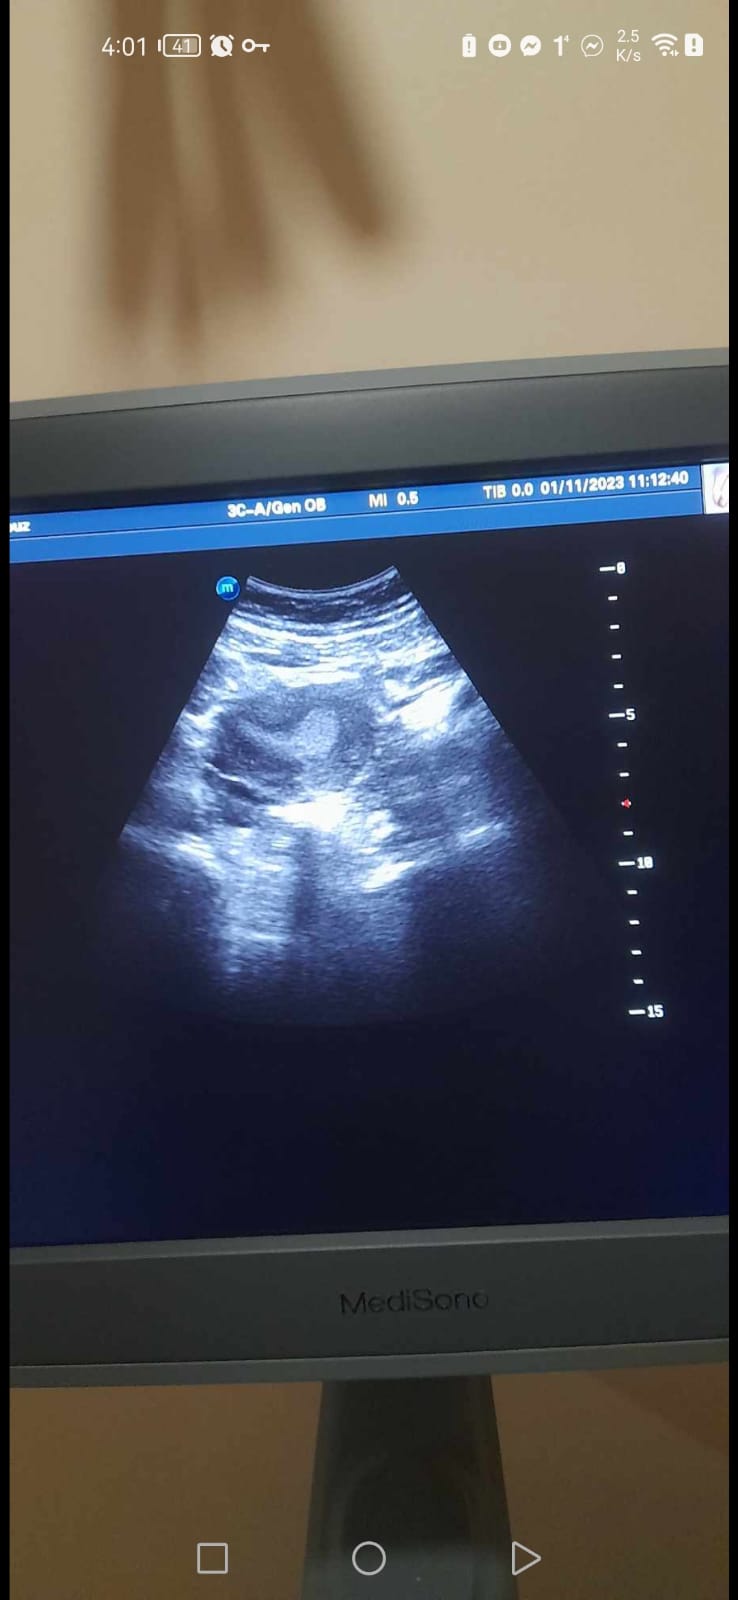

هل التكيس على المبايض خطير وما مدى خطورته؟ وهل علاجه يسير؟